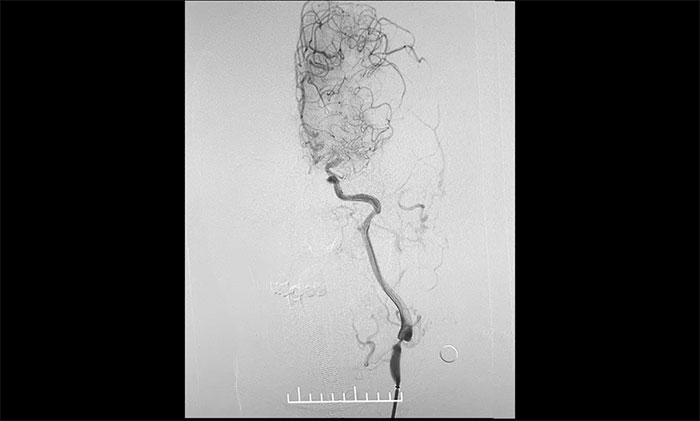

▲ 颈动脉重度狭窄解除,打通大脑生命线

术中,席刚明教授、王贵平博士克服血管迂曲困难,经过多次尝试,多次球囊扩张、“按摩”后,最终顺利释放密网支架至左颈内动脉眼动脉段、左颈内动脉床突段、左颈内动脉海绵窦段。造影及3D造影见,动脉瘤瘤内造影剂明显滞留,左颈内动脉、左大脑前动脉显影可,载瘤动脉通畅,获得了理想的血管重建。复查造影,左颈总动脉造影见左颈总动脉、左颈内动脉、左大脑前动脉显影可。CT见支架打开贴壁满意,XperCT未见颅内出血,手术圆满完成,顺利拆除“不定时炸弹”并打通大脑生命线。